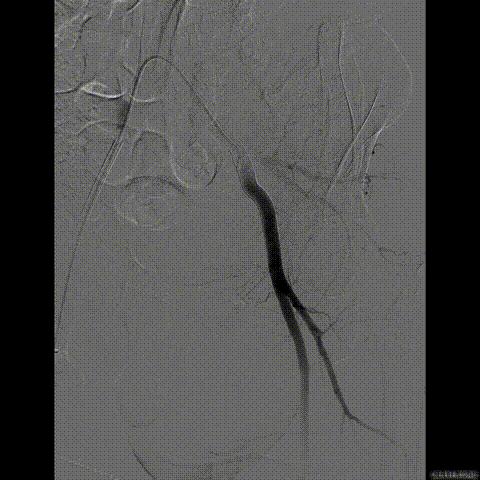

行急诊手术 腹主动脉及左侧股动脉造影

左侧股动脉见造影剂外渗

球囊压迫后植入覆膜支架

复查造影